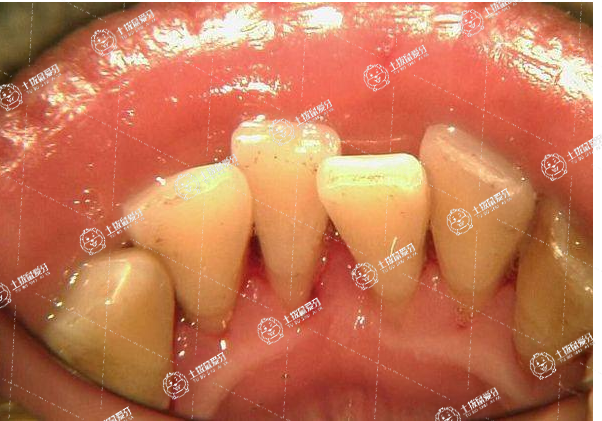

矯正牙齒擁擠可以通過佩戴牙齒矯正器來進行矯正治療,主要包括鋼絲牙套和隱形牙套。對于牙齒擁擠比較嚴重的人群,在矯正之前一般需要先拔出一顆牙齒給牙齒留出來空隙,然后再做牙齒矯正治療,這樣才能使牙齒快速的恢復到正常的位置。鋼絲牙套主要是將鋼絲固定在牙齒上面的,通過鋼絲產(chǎn)生的拉力能夠使牙齒恢復到正常的形態(tài)以及狀態(tài)。在做完治療之后,要注意口腔的衛(wèi)生和清潔,盡量避免咀嚼一些比較硬的食物。

1、采用傳統(tǒng)的矯正方法,把固定裝置粘固于牙齒上,患者不能自己摘戴,要醫(yī)師裝拆、調(diào)整加力。每個月復診一次,醫(yī)生逐漸加力使牙齒移動,達到設(shè)計的理想狀態(tài),正畸工作基本結(jié)束。拆除矯治器以后還要戴一段時間保持器,以鞏固正畸成果,防止復發(fā)。

2、可以帶牙套來進行矯正,這是一種比較可行的辦法,這種方法時間最長,大概要兩到三年。牙齒矯正期間還要不時的回醫(yī)院檢查。這種方式對未成年人是最合適的,成年人雖然也可以,但矯正的時間會更長。

3、對于牙齒擁擠不齊還可以進行手術(shù)治療,這種方法只是針對于前兩種方法無法矯正的時候才會用到。像那些骨性暴牙那樣的也就只能動手術(shù)了,這種手術(shù)風險小,費用一般,需要到正規(guī)專業(yè)的醫(yī)院?;蛘哌M行隱形矯正,就是把矯治器全部安裝于牙齒的舌側(cè)面進行正畸治療,因此也叫作舌側(cè)正畸。這種正畸方法是從外面看不見矯治器,正畸治療期間仍然可以進行正常的社交和職業(yè)活動。不知不覺中改變了牙齒排列,改變了面部形象。